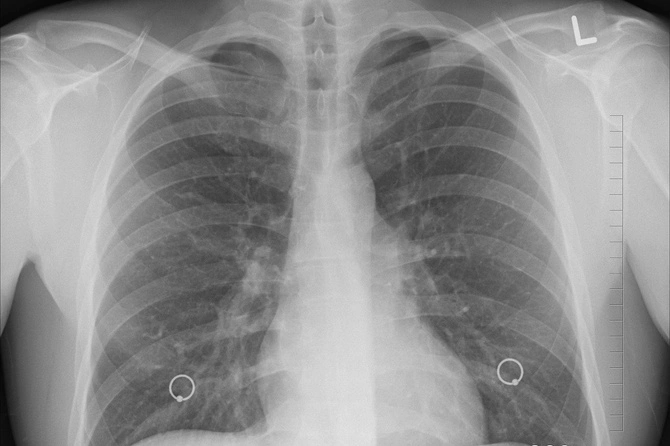

Врач-инфекционист Первого Санкт-Петербургского медицинского университета имени Павлова Оксана Станевич сообщила об увеличении числа пациентов с COVID-19, у которых происходят спонтанные «разрывы легких».

По ее словам, разрывы чаще всего происходят в наиболее воспаленной области легкого. Но порой достаточно даже небольшого числа участков «матового стекла».

«При этом осложнении воздух скапливается между листками плевры, наступает коллабирование легкого, оно спадается и нарастает дыхательная недостаточность. Это уже острая хирургическая ситуация, необходимо дренировать легкое, выпускать воздух», — пояснила Станевич в разговоре с «Лентой.ру».

«В самом начале пандемии, в первую волну, такого не было. А уже во вторую волну мы начали отмечать такие явления. Есть гипотеза, что коронавирус приобрел мутации, вызывающие более сильный воспалительный ответ. Возможно, влияют какие-то генетические особенности», — подытожила эксперт.